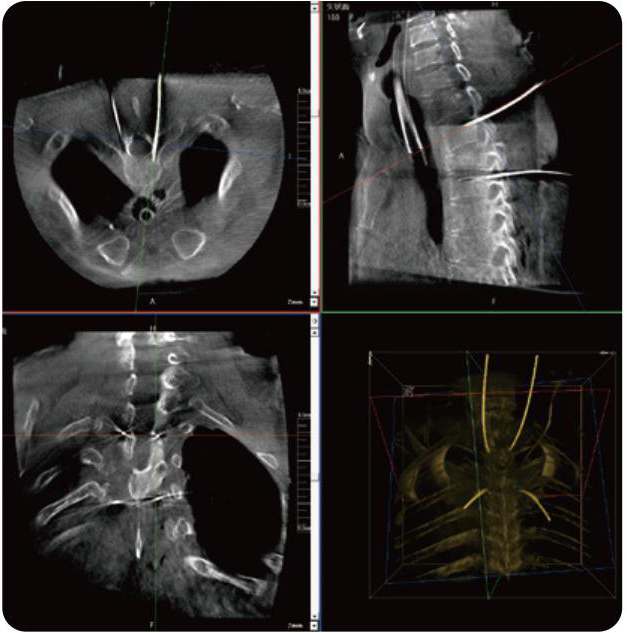

PL300B可应用于多节段脊柱外科手术,辅助医生定位病灶部位,为脊柱外科手术(经皮椎体成形术、椎弓根螺钉内固定术等术式)提供术前手术流程规划、入钉位置、角度可视化引导,模拟仿真入钉辅助。

PL300B搭配糖心vlog 自主研发生产的平板3D C形臂,借助一体化自适应配准( 轨迹配准)技术,通过追踪C形臂三维采集轨迹,自动完成图像坐标建立和系统坐标配准。配准精度更高,操作步骤少,系统运作效率高。